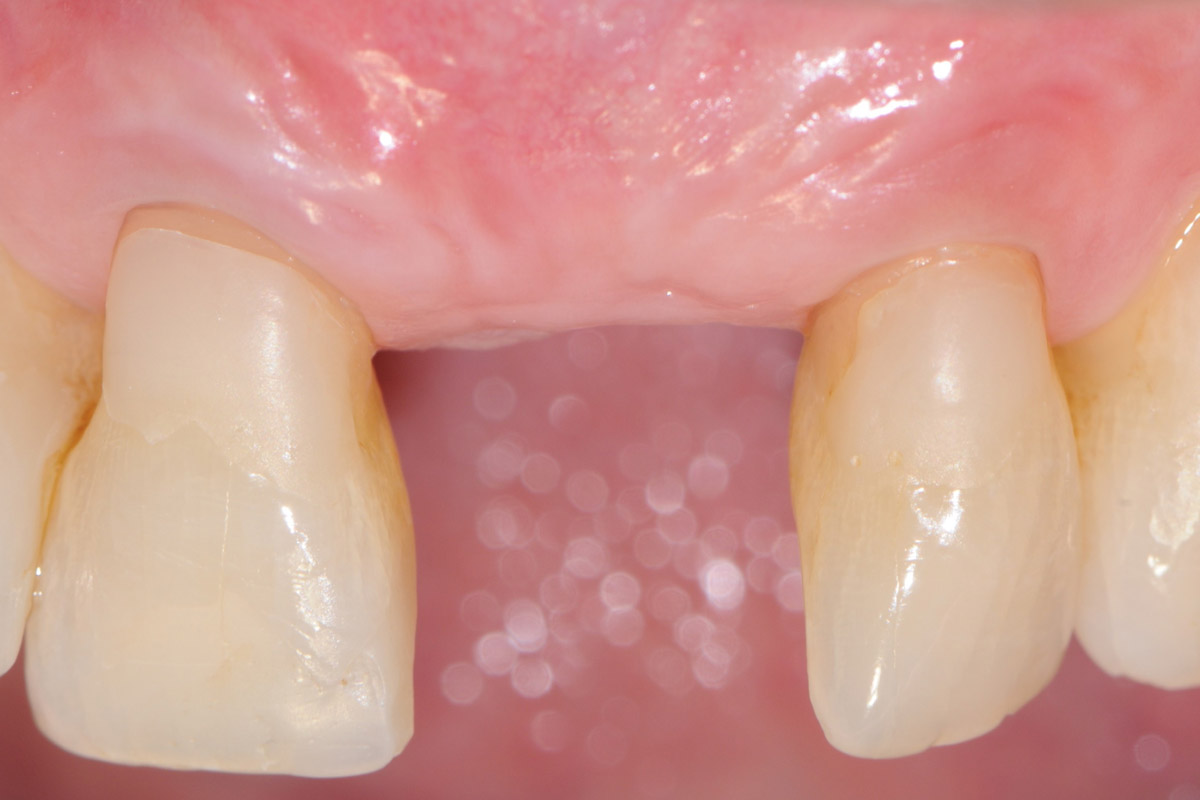

15/18 - 20 weeks after surgery perfect aesthetic integration of newly formed keratinized tissue with surrounding tissueTooth extraction and socket sealing with mucoderm® - Dr. A. Rossi